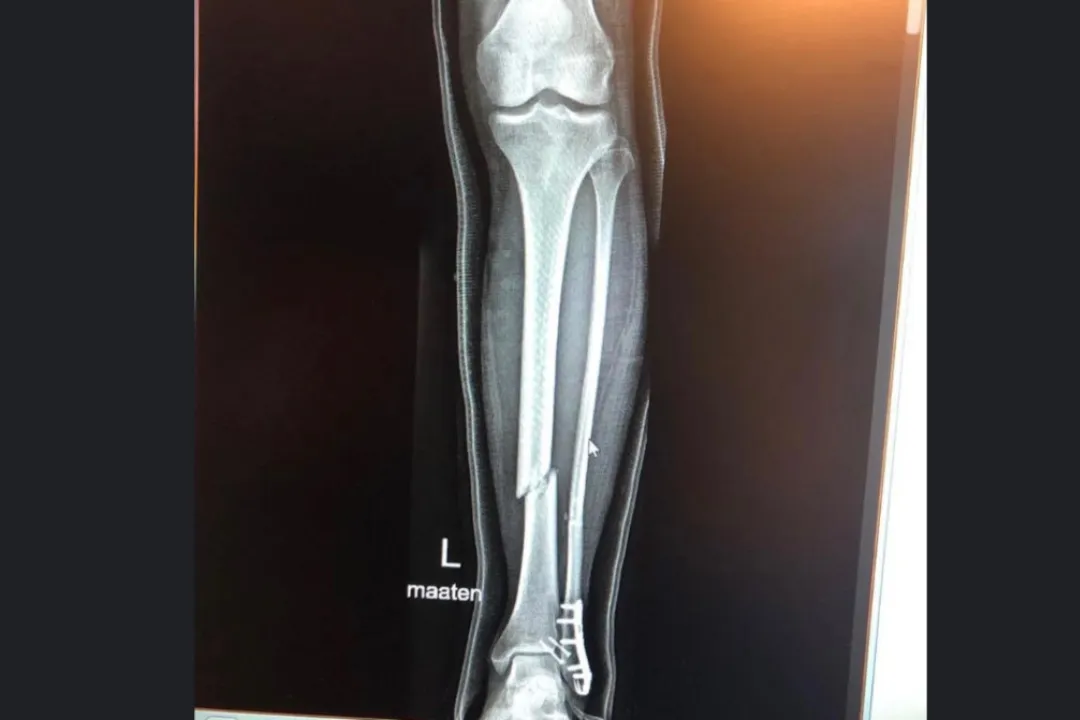

Brutte notizie per Mika Kallio a meno di una settimana dal primo test MotoGP in Qatar. Il collaudatore della KTM si è infortunato mentre guidava una moto sul ghiaccio in Finlandia. Subisce uno stop di sette-otto settimane, quindi salterà l'intero tour di Losail. Il 16-17 febbraio il tester finlandese aveva testato la nuova RC16 sul circuito di Jerez, impegno dove erano presenti anche il collega Dani Pedrosa, oltre a Stefan Bradl e Michele Pirro. Kallio ha riportato la frattura di tibia e perone durante l'allenamento in moto pur non riportando una caduta. "Ora sto aspettando l'operazione, la tibia e il perone devono essere riparati", ha scritto sui social. “Sfortunatamente, a volte un errore piccolo e innocuo ha conseguenze dolorose. Non è quello che avevo in mente per la 'Ice Road Race' di oggi".

Foto e Video: Instagram @mikakallioofficial